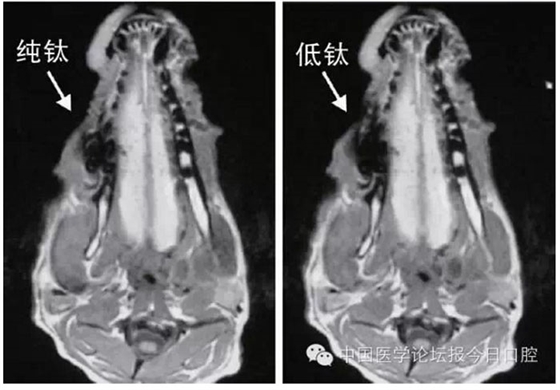

文獻(xiàn)研究中常使用的金屬包括鎳鉻合金、鈷鉻合金、低鈦合金、純鈦、金合金、金鈀合金、銀鈀合金等成分如表所示。大量研究得出近乎一致性的結(jié)論。金合金、金鈀合金、銀鈀合金對(duì)MRI影響甚微,與全瓷材料、丙烯酸樹(shù)脂極為相似,表現(xiàn)為修復(fù)體影像邊緣光滑、無(wú)變形、無(wú)偽影;純鈦金屬對(duì)MRI影響較小,接近于全瓷材料;但有的研究卻發(fā)現(xiàn)純鈦在核磁共振場(chǎng)中也產(chǎn)生偽影,但偽影涉及的掃描層數(shù)較少;低鈦合金(鈦合金)對(duì)MRI影響較大,介于純鈦和鎳鉻合金之間,中度偽影;鎳鉻合金、鈷鉻合金對(duì)MRI影響很大,鈷鉻合金更甚;表現(xiàn)為重度偽影、圖像扭曲變形(圖1、圖2)。不難看出,對(duì)MRI影響,全瓷材料、樹(shù)脂材料<金合金等貴金屬<純鈦<低鈦合金<鎳鉻合金<鈷鉻合金。有研究發(fā)現(xiàn)鈷鉻合金橋偽影大小與修復(fù)體長(zhǎng)軸一致,影響范圍為固定橋近遠(yuǎn)中徑2倍,頰舌徑的4倍;相同外形金屬修復(fù)體厚度增加,偽影增加。單個(gè)金屬樁核偽影可波及到上頜竇、牙槽骨、舌體、舌下腺等組織器官,但對(duì)眼底、眼內(nèi)容物、腦組織和頸椎成像基本無(wú)影響。

圖2 4種金屬冠在犬MRI檢查中的影響,圖片引自《實(shí)用口腔醫(yī)學(xué)雜志》2014第30期《4種金屬冠對(duì)磁共振成像影響的對(duì)比研究》一文,作者高嵐等